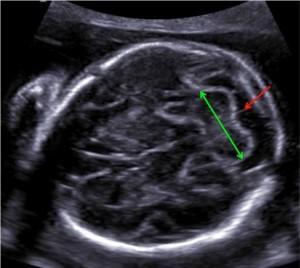

این تصویر در حال بررسی سطح مقطع جنین در سطح مخچه (CRBL) در هفته 21 بارداری را نشان میدهد. قطر مخروطی مرزی (خط سبز) و اندازه cisterna magna (فلش قرمز) باید در این نقشه اندازه گیری شود. آناتومی مغزی در قسمت خلفی مغز جنین نیز باید اندازه گیری شود.